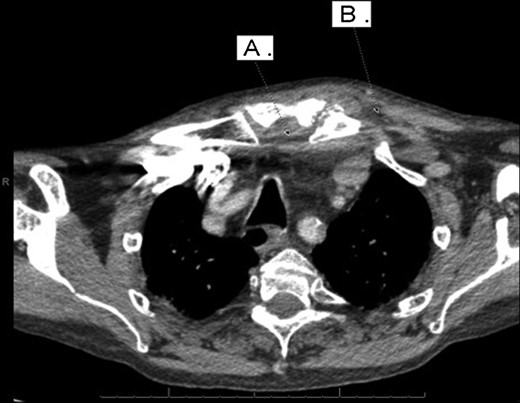

With a working differential of parapharyngeal space infection and possible malignancy, the patient was referred for a computed tomography (CT) scan of the neck and thorax with contrast. The patient was also started empirically on intravenous co-amoxiclav as treatment for neck space collection. CT imaging, performed 24 h after admission, revealed no evidence of malignancy or indeed any paraphayrngeal space collection. Few small lymph nodes were noted on the left side of the neck, but were deemed to be reactive in nature, and left vocal cord palsy was evident (Fig. 1). The key finding was that of a left sternoclavicular joint collection and closely associated superficial anterior chest wall, soft tissue swelling and oedema (Fig. 2). This inflammatory process was also noted deep to the manubrium and sternum and extending somewhat into the mediastinum with evident enlarged mediastinal lymph nodes (Fig. 3). The CT findings were in keeping with SSA with associated superficial and deep tissue inflammation and oedema. With no other cause found, the vocal cord palsy was attributed to the inflammation within the mediastinum, which in turn was caused by superficial burn from hot water bottle use.

Computed tomography. A 67-year-old male with SSA. Findings: left sternoclavicular joint collection and closely associated superficial anterior chest wall, soft tissue swelling and oedema. The oedema can be seen to be spreading into the chest. Technique: contrast-enhanced axial CT of the neck and thorax.